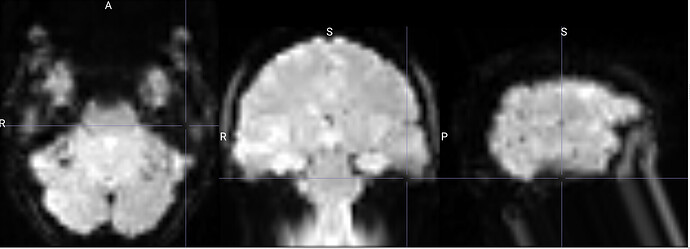

I am running fmriprep for the first time, and my preproc_bold.nii files have a weird distortion extending from the cerebellum for a few slices, it is basically a copy of what seems like the final slice, extending anteriorly.

The copied slices are overlapping with the superior slices, likely messing with the voxels.

images showing how it extends anteriorly: